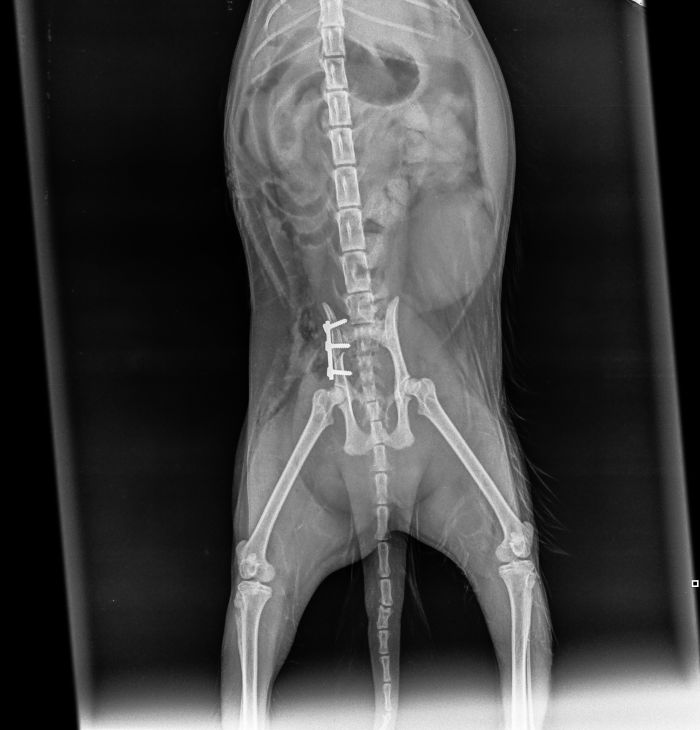

Plattenosteosynthese

Hierbei wird eine Metallplatte  als "Kraft (über-) träger zwischen den Knochenbruchstellen verwendet. Es gibt es eine Vielzahl an Platten ( Abstützplatte, Neutralisationsplatte, Kompressionsplatte, etc.) mit diversen Größen und Längen. Die Metallplatte wird mit speziellen Schrauben (z.B.: Corticalisschrauben / Spongiosaschrauben / ...) am Knochen fixiert.

Fall 1